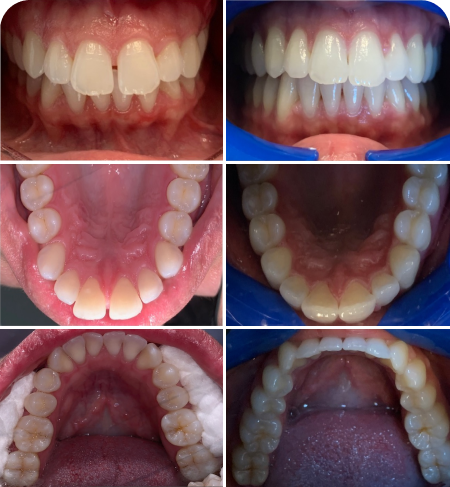

Veneer

Cases

At Tooth, we provide all General Dentistry services, and 99 percent of all other Dental specialty services under one roof. Our goal is to provide all our patients with caring, supportive dental visits so you can feel loose and relaxed like we are family. We strive to stand out as a Trusted Practice that gives back to our community and the Greater Sacramento Area and provides the highest quality of Dentistry backed by Dr. Badyal’s guarantee on all Procedures.